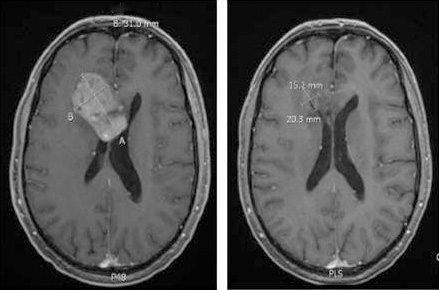

Hirntumore bei Kindern: Eine neue Hoffnung für kleine Krebspatienten

Die Überlebenschancen von krebskranken Kindern sind stark gestiegen. Manche Hirntumore bleiben aber schwer behandelbar. Ein neuer Therapieansatz zeigt Erfolge.